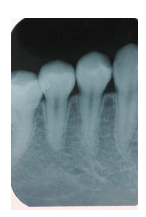

病例三:

19歲女性病人,小時候左下顎第二小臼齒不明原因被拔除,導致第一臼齒往前傾倒,如圖3A、3B 所示。一年前齒顎矯正醫師將第一大臼齒以矯正力量漸漸扶正,如圖3C所示。由於病人的右下顎第二大臼齒因為矯正需要必須拔除,因此轉診而來,希望將右下顎第二大臼齒(如圖3D),移植至左下顎第二大臼齒之缺牙區,如圖3E。圖3F為術後一個禮拜的X光片,牙齒已經根管治療。圖3G、3H為術後一年的情況,牙根尖骨頭已完全再生回來,牙周情況良好,咬合正常

圖3A

圖3D

圖3E

圖3F

圖3G